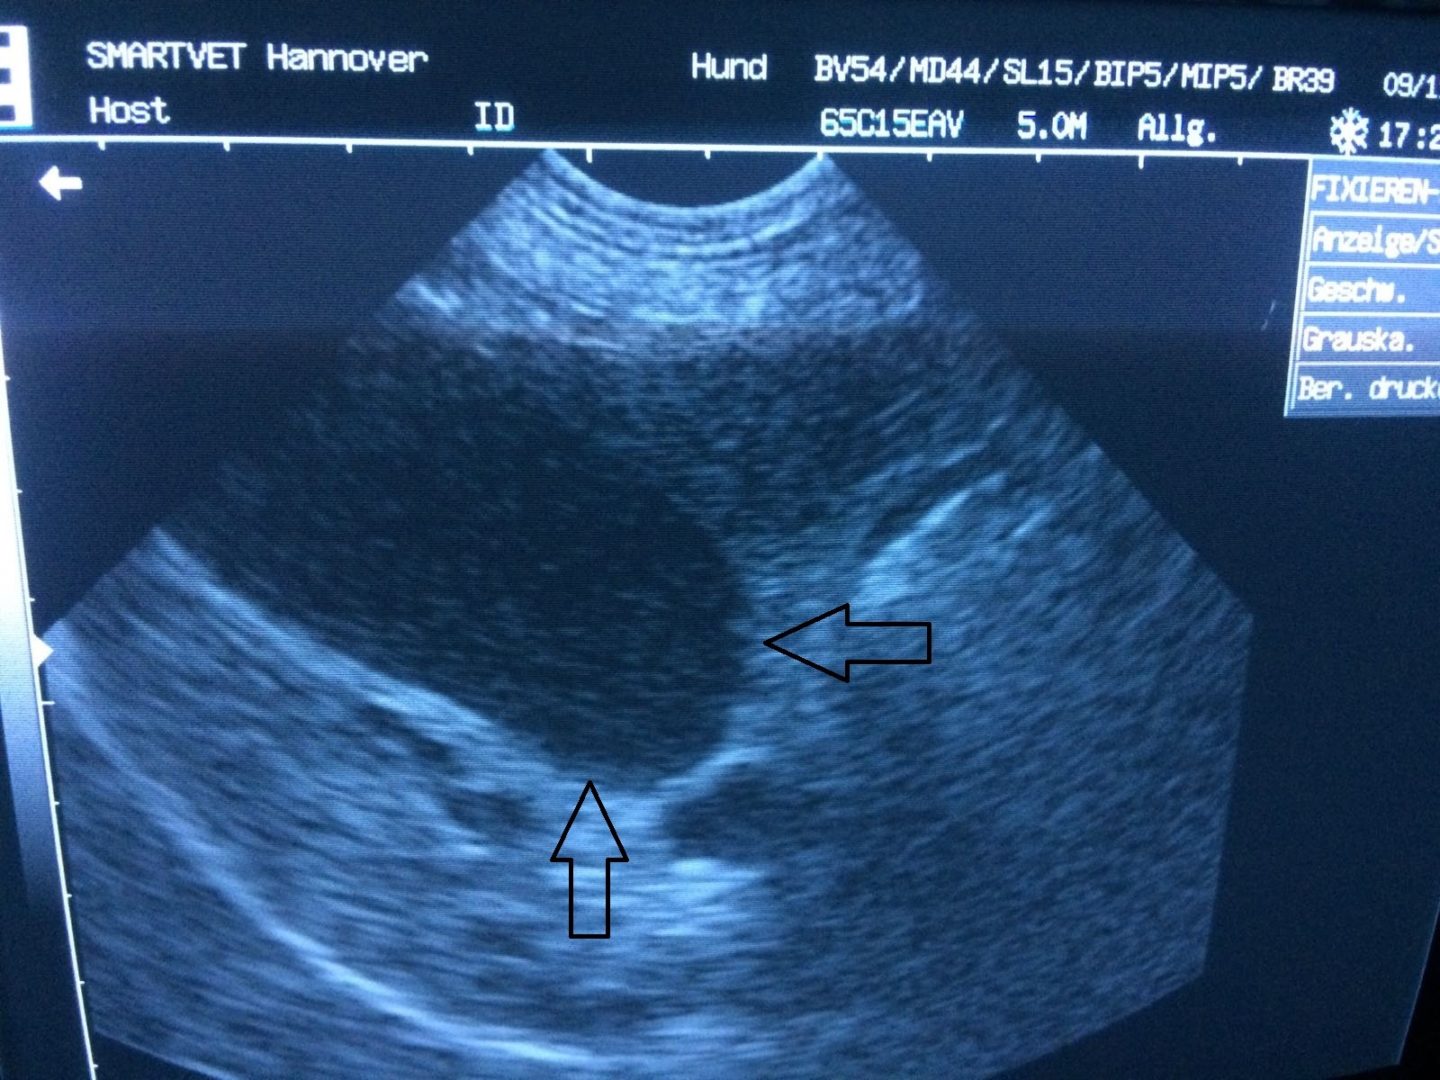

Ein Ultraschall sollte etwas Licht ins Dunkel bringen. Von der Textur, der inneren Beschaffenheit des Gewebes, sah die Leber im Ultraschall trotz ihrer leichten Größenzunahme vorbildlich aus - ohne Vernarbungen, ohne Tumore. Einzige Auffälligkeiten waren Sludge in der Gallenblase (eingedickte Galle), dazu eine Entzündung im Lebergewebe rund um Chickos Gallenblase herum und eben eine Stauung der Gallengänge.